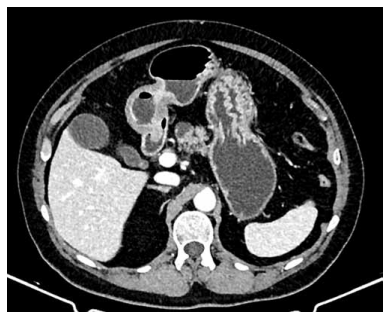

Paciente do sexo feminino, de 31 anos, apresenta dor em hipocôndrio direito, icterícia, colúria e acolia fecal há duas semanas. Exames laboratoriais mostram elevação de fosfatase alcalina, GGT e bilirrubina direta. A ressonância magnética

evidencia dilatação cística extensa da via biliar extra-hepática e intra-hepática, associada a múltiplas imagens sugestivas

de litíase intra-hepática. Foi realizada CPRE com colocação de próteses plásticas, sem melhora significativa dos níveis

de bilirrubina.

Exames de imagem apresentados a seguir:

(Arquivo pessoal; imagem usada com autorização)

Considerando o quadro apresentado e as opções terapêuticas, qual é a conduta cirúrgica definitiva de escolha correta?